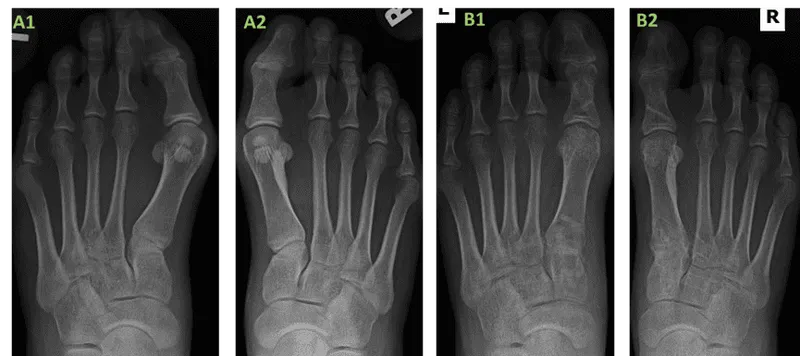

Lateral deviation of great toe (valgus) & medial deviation of 1st metatarsal (varus).

- Key Angles:

- HVA (Hallux Valgus Angle): Normal < 15°

- IMA (Intermetatarsal Angle): Normal < 9°

- DMAA (Distal Metatarsal Articular Angle): Normal < 10°

- Severity (approx.):

- Mild: HVA 15-20°, IMA 9-11°

- Moderate: HVA 21-39°, IMA 12-17°

- Severe: HVA ≥ 40°, IMA ≥ 18°

⭐ The position of the tibial sesamoid relative to the first metatarsal head is a key radiographic indicator of hallux valgus severity (Hardy and Clapham classification).